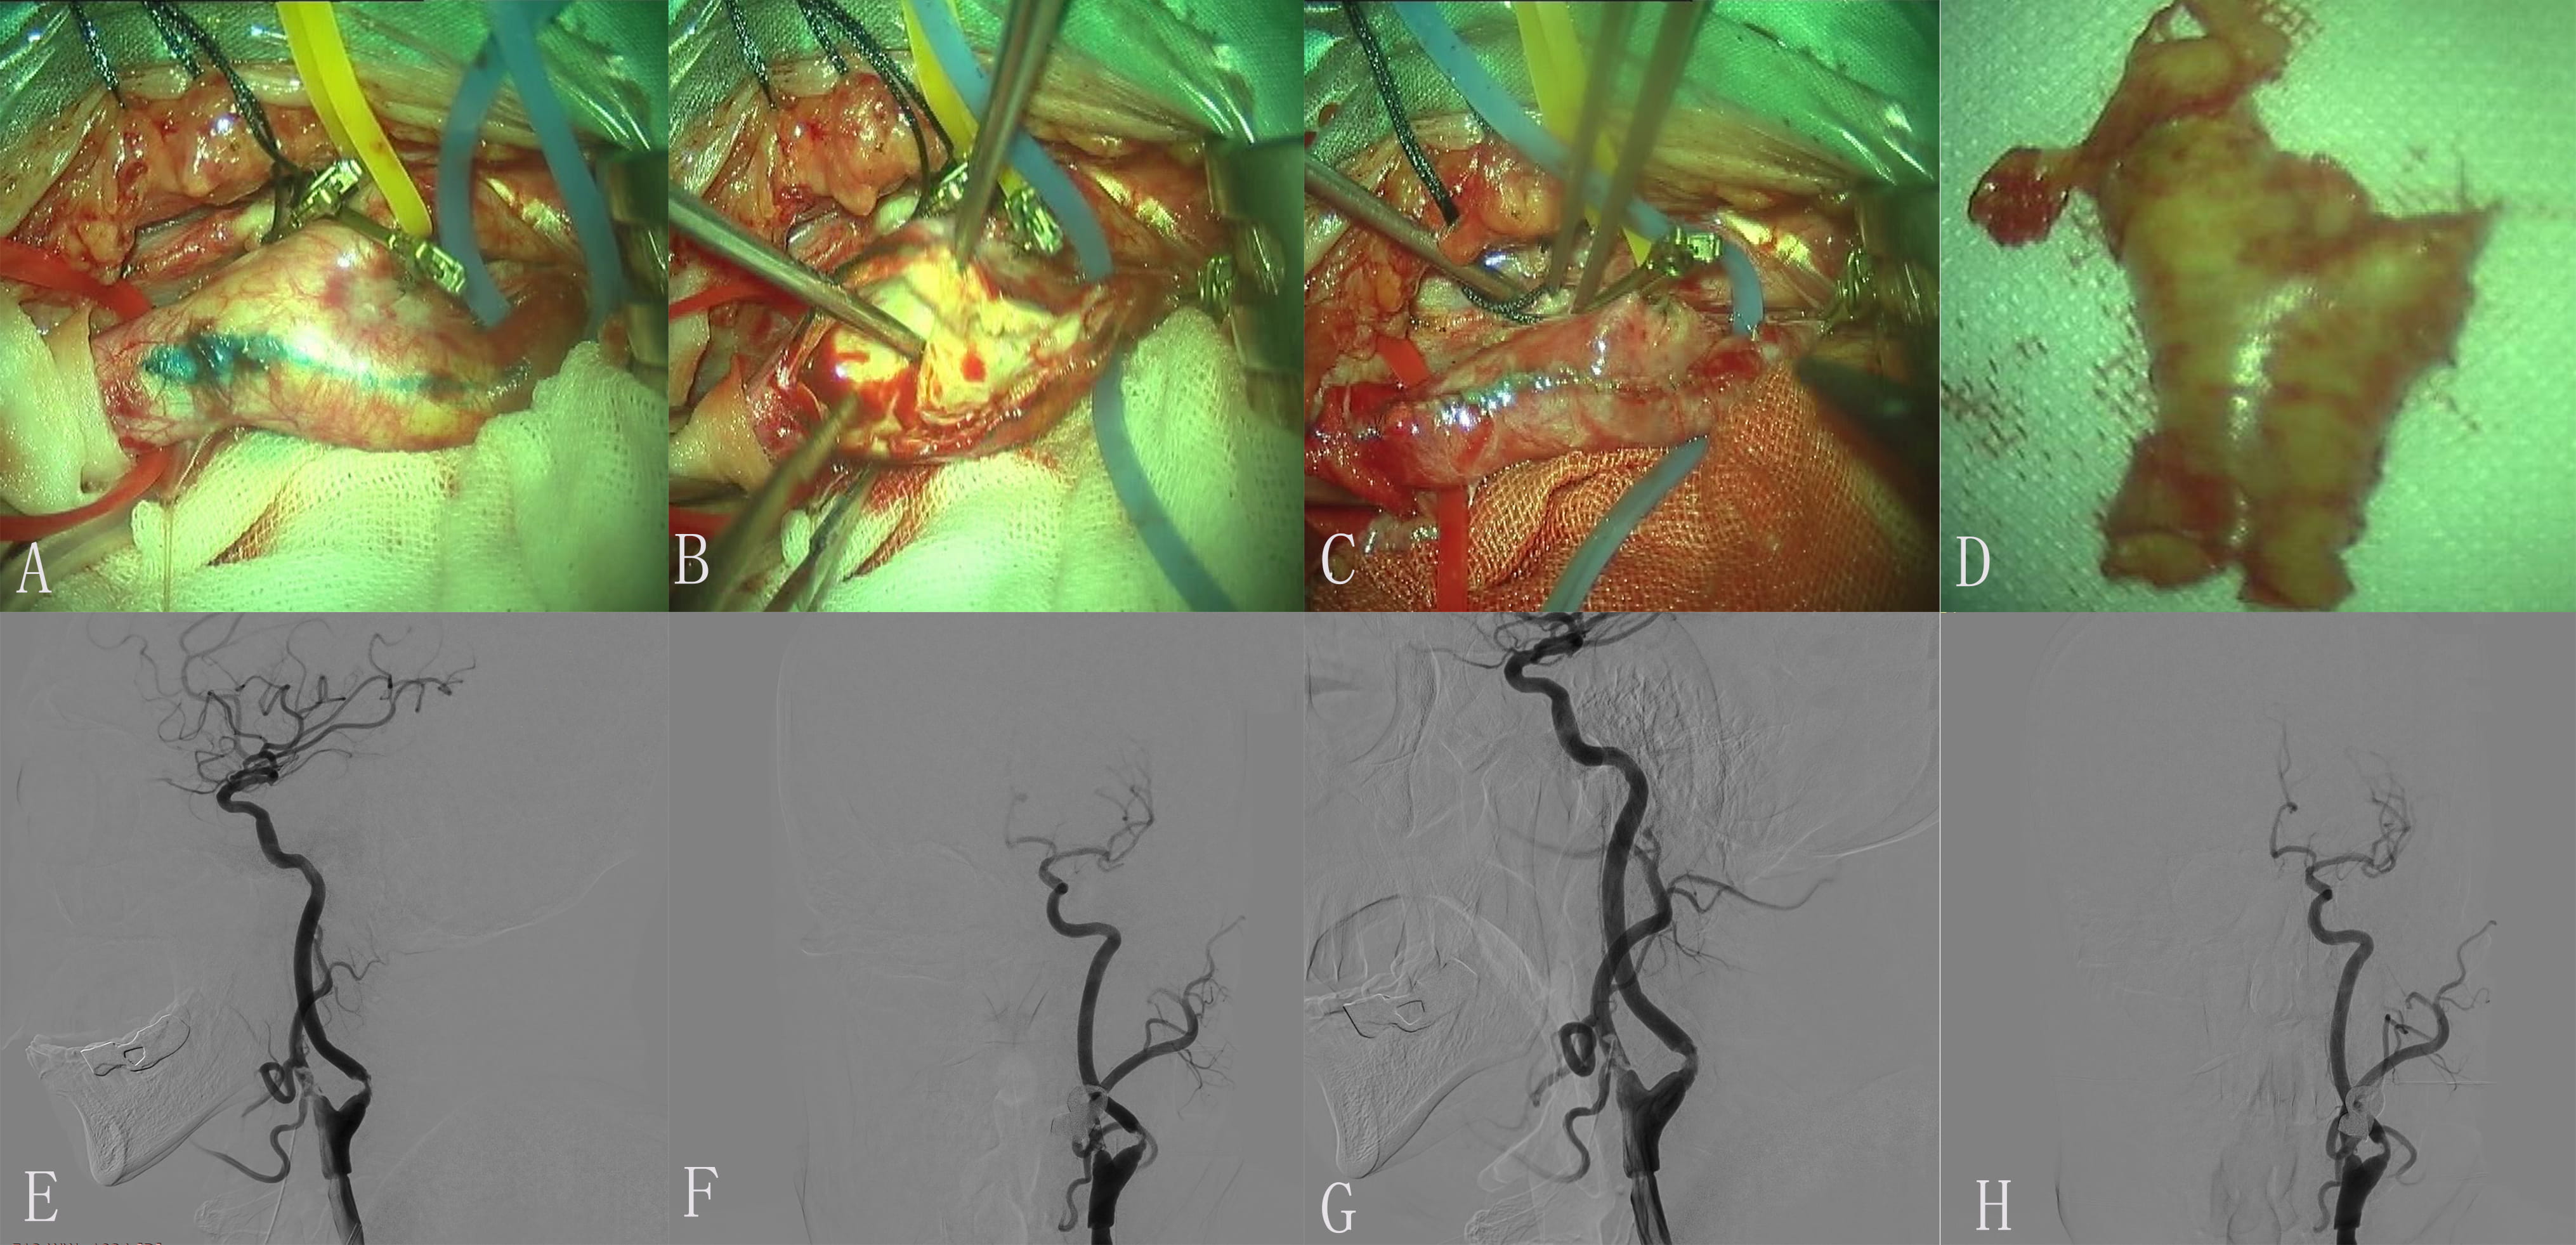

Fig. 3.Images of Case 3. Color Doppler ultrasonography of carotid artery on admission showed initial severe stenosis of the left internal carotid artery (ICA). The stenosis is greater than 90%. (A) Each branch was blocked by exposed responsibility carotid artery. (B) The endometrium of the common carotid artery (CCA) was dissected longitudinally and presented plaque. (C) Incision suture. (D) Intimal plaque. (E,F) Embolus was formed in a position with a large angle of carotid endarterectomy (CEA). (G,H) The imaging of ICA was significantly improved after 0.5 mg tirofiban was administered to the artery.